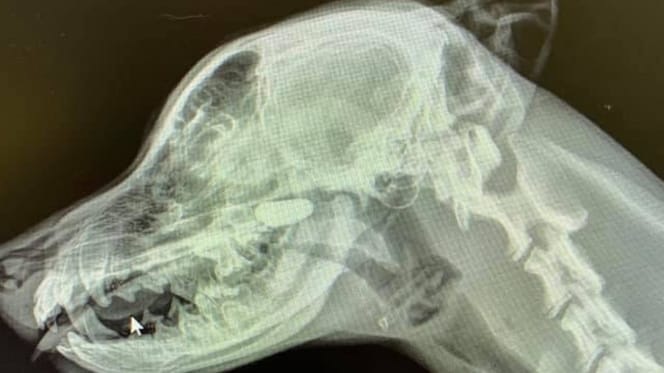

Radiografia della testa di un cane

© Sarah Yuki @Iloveveterinarymedicine / Facebook

Quindi la veterinaria continua a cercare e fa eseguire diverse radiografie del  cane. Prima del torace, ma in questa immagine Sarah non riesce a riconoscere nulla di sospetto. Quindi ordina di eseguire una radiografia laterale della testa e del collo. E questo si rivela un colpo vincente!

Nello spazio nasale è chiaramente visibile un corpo estraneo che lì non dovrebbe assolutamente esserci. Alla fine si scopre essere un sasso che il cucciolo in qualche modo si è infilato nel naso. Dopo la rimozione, il piccolo Labrador è immediatamente migliorato.